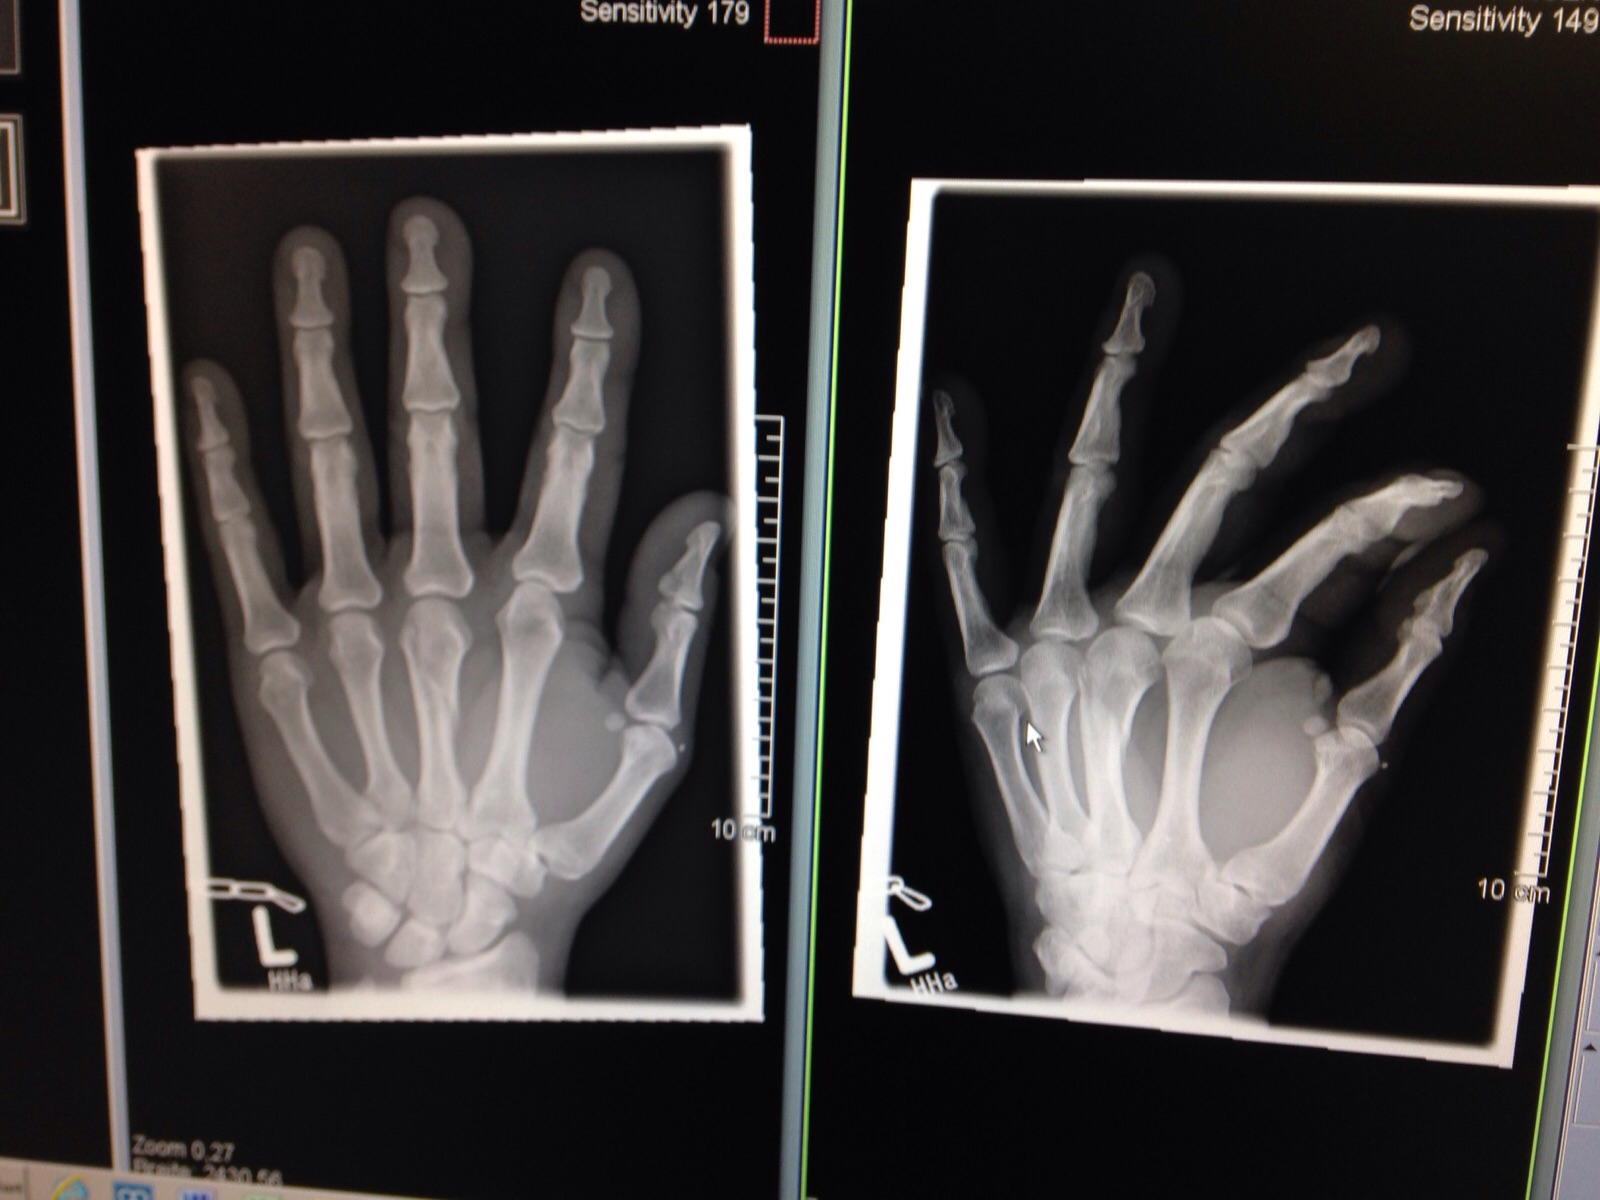

Die Prüfungsvorbereitungen unseres Vereinsmitglied Paul sind am Donnerstag jäh unterbrochen worden. Beim Training in Hinblick auf die DAN Prüfungen von Franzi und Paul, ist es beim Freikampf bei einem unglücklichen Zusammentreffen zwisches Franzis Fuß und Pauls Hand zum Bruch der Selbigen gekommen. Ärgerlich, aber "shit happens". Aufgeschoben ist nicht aufgehoben. Der Termin zur DAN- Prüfung bei unserem Bundestrainer Eftimios karamitsos am 05.12.2015 ist für Paul nun selbstverständlich nicht mehr zu halten (siehe Bilder). Aber schon Anfang 2016 ergeben sich eine ganze Reihe weiterer Püfungstermine zum 1. DAN. Der Verein wünscht dir gute und recht schnelle Besserung.